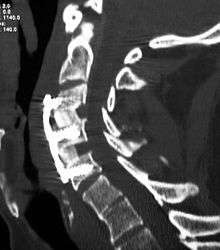

The neurosurgeon or orthopedic surgeon enters the space between two discs through a small incision in front (= anterior) of and at the right or left side of the neck. The disc is completely removed, as well as arthritic bone spurs. The disc material, pressing on the spinal nerve or spinal cord, is then completely removed. The intervertebral foramen, the bone channel through which the spinal nerve runs, is then enlarged with a drill giving the nerve more room to exit the spinal canal.

To prevent the vertebrae from collapsing and to increase stability, the open space is often filled with bone graft, taken from the pelvis or cadaveric bone. The slow process of the bone graft joining the vertebrae together is called "fusion". Sometimes a titanium plate is screwed on the vertebrae or screws are used between the vertebrae to increase stability during fusion, especially when there is more than one disc involved.